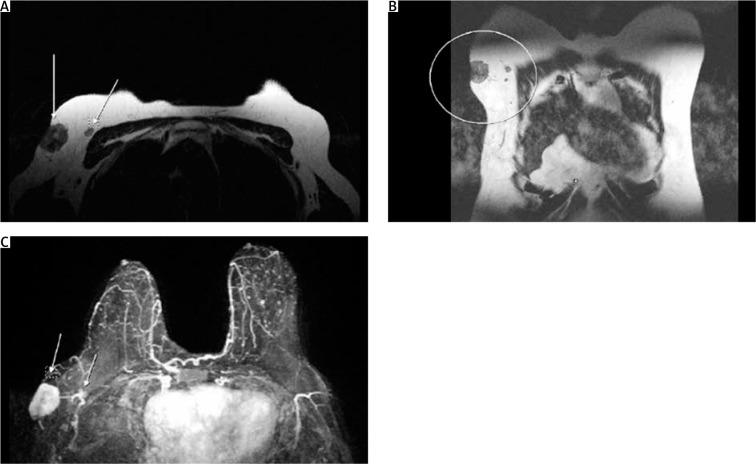

Carcinoma of the accessory breast tissue (CABT) is an extremely rare occurrence, representing 0.3% of all breast malignancies. A 65-year-old, postmenopausal woman was referred to our Breast Clinic complaining of a palpable, growing, and painful mass in her right axilla. Physical examination revealed a palpable tender mass, approximately 3 cm in size, visibly infiltrating the overlying skin area, while physical examination of the breast revealed no palpable lesions. Core biopsy of the mass was promptly scheduled, and the histological report came back positive for Nottingham Grade II NST invasive carcinoma of the breast. The patient underwent breast-conserving surgery and concomitant axillary lymph node dissection (ALND) for removal of the malignant mass. Care was taken to preserve the axillary vein and the long thoracic nerve. Closure of the axillary incision required mobilization of skin flaps to ensure optimal cosmetic results. Despite the ectopic breast tissue being a largely benign and infrequent occurrence, the breast surgeon must remain vigilant for the possibility of CABT development. At any rate, further epidemiological studies incorporating as many patients as possible are required in order to formulate recommendations on the management and prognosis of CABT. Until such guidelines exist, excision of the carcinoma, along with ALND performance, is a reasonable and justified approach to the surgical treatment of CABT.

副乳腺组织癌(CABT)极为罕见,占所有乳腺恶性肿瘤的0.3%。一名65岁的绝经后女性因右腋窝可触及、不断增大且疼痛的肿块被转诊至我们的乳腺诊所。体格检查发现一个可触及的压痛肿块,大小约3厘米,明显浸润了上方的皮肤区域,而乳房体格检查未发现可触及的病变。随即安排了肿块的核心活检,组织学报告显示为诺丁汉二级非特殊类型浸润性乳腺癌阳性。患者接受了保乳手术及同期腋窝淋巴结清扫术(ALND)以切除恶性肿块。术中小心保留了腋静脉和胸长神经。腋窝切口的缝合需要游离皮瓣以确保最佳的美容效果。尽管异位乳腺组织大多为良性且不常见,但乳腺外科医生必须对CABT发生的可能性保持警惕。无论如何,需要开展纳入尽可能多患者的进一步流行病学研究,以便就CABT的管理和预后制定建议。在有此类指南之前,切除癌肿并进行ALND是CABT手术治疗的合理且正当的方法。